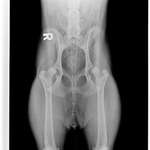

Ich habe das Gefühl, dass meine 8,5 Jahre alte Hündin immer engmaschiger Läufig und Scheinträchtig wird.

Ihre letzte Läufigkeit ging bis Ende Oktober, war dann die ersten zwei Dezemberwochen über Scheinträchtig und zeigt nun wieder die ersten Anzeichen einer Läufigkeit.